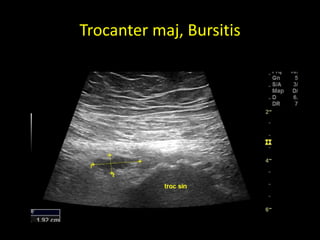

The greater trocanter, Trocanter maj.

Trocanter maj, Bursitis

The greater trocanter,Trocanter maj.